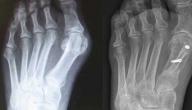

• تصوير الأشعة (X-ray): تكشف صورة الأشعة عن موقع الكسر وعن درجته وحدّته، مما يفيد في تحديد سبل العلاج الممكنة.